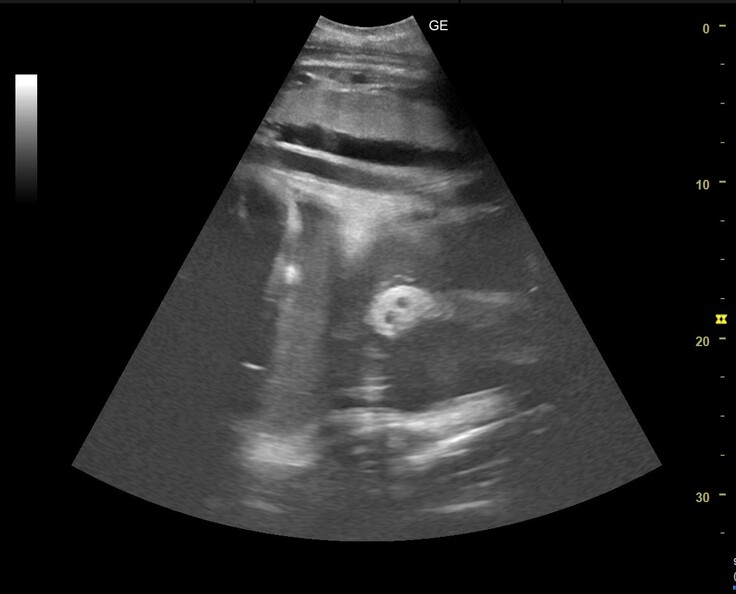

2月5日に、メイの超音波検診を行いました。

今回はお腹の中の胎子がよく動いていて、お願い止まってと念じながらの検査でした。

そんな動き回る胎子をなんとか確認していたところ、見ていた職員がお!と声をあげました。

見えたものがこちらです。

写真中央やや右に見える、白い楕円と中の二つの穴。胎子の鼻の断面だと考えています。

サイズは長径が4㎝程度、短径が3㎝程度でした。長い鼻のどの部分かはわかりません。これまでの検診ではじめて、わかりやすい「ゾウらしい形」を捉えることができました。

動き回る胎子の診断は難しかったのですが、へその緒の様子から胎子はちゃんと生きていることが確認できました。